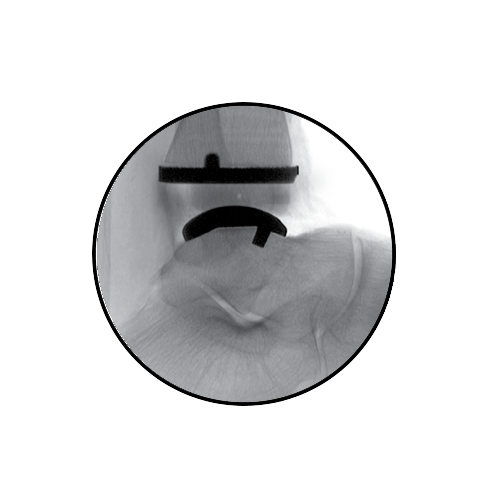

AP Spacer Guide

The AP Positioning Spacer establishes optimal AP bone coverage